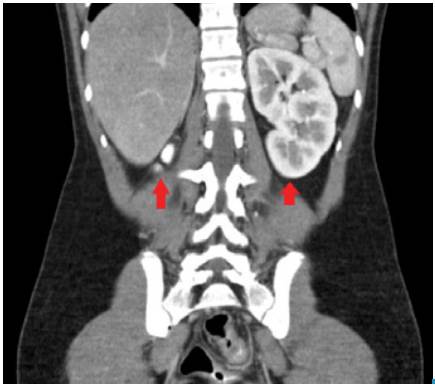

Considering the symptoms, pregnancy or infection of the urogenital tract were suspected; paraclinical results showed negative pregnancy test, blood count with leukocytosis without neutrophilia (leukocytes 15 300 and neutrophils 61.6%), without anemia (hemoglobin 14.2 gr/L, hematocrit 41%) and platelets 433 000/uL. Urinalysis did not suggest urinary tract infection. Transvaginal ultrasound and abdominal pelvic tomography were requested, revealing uterus didelphys (Figure 1) and renal agenesis (Figure 2).

Coronal computed tomographic (CT) scan that shows the left kidney and right renal agenesis.

Figure 2: Coronal computed tomographic (CT) scan that shows the left kidney and right renal agenesis.

Source: Document obtained during the study.